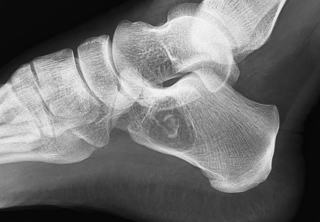

| X線 | 明瞭な透亮像。単房性(単純性)〜時に隔壁状。骨皮質菲薄化あり。病変周囲に反応性硬化。 |

| 特徴的所見 | “fallen fragment sign”:病的骨折後に骨片が嚢胞内に落ち込む像。踵骨では比較的診断的価値あり。 |